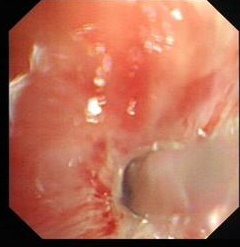

图片1 治疗前狭窄的右主气管痰液栓塞